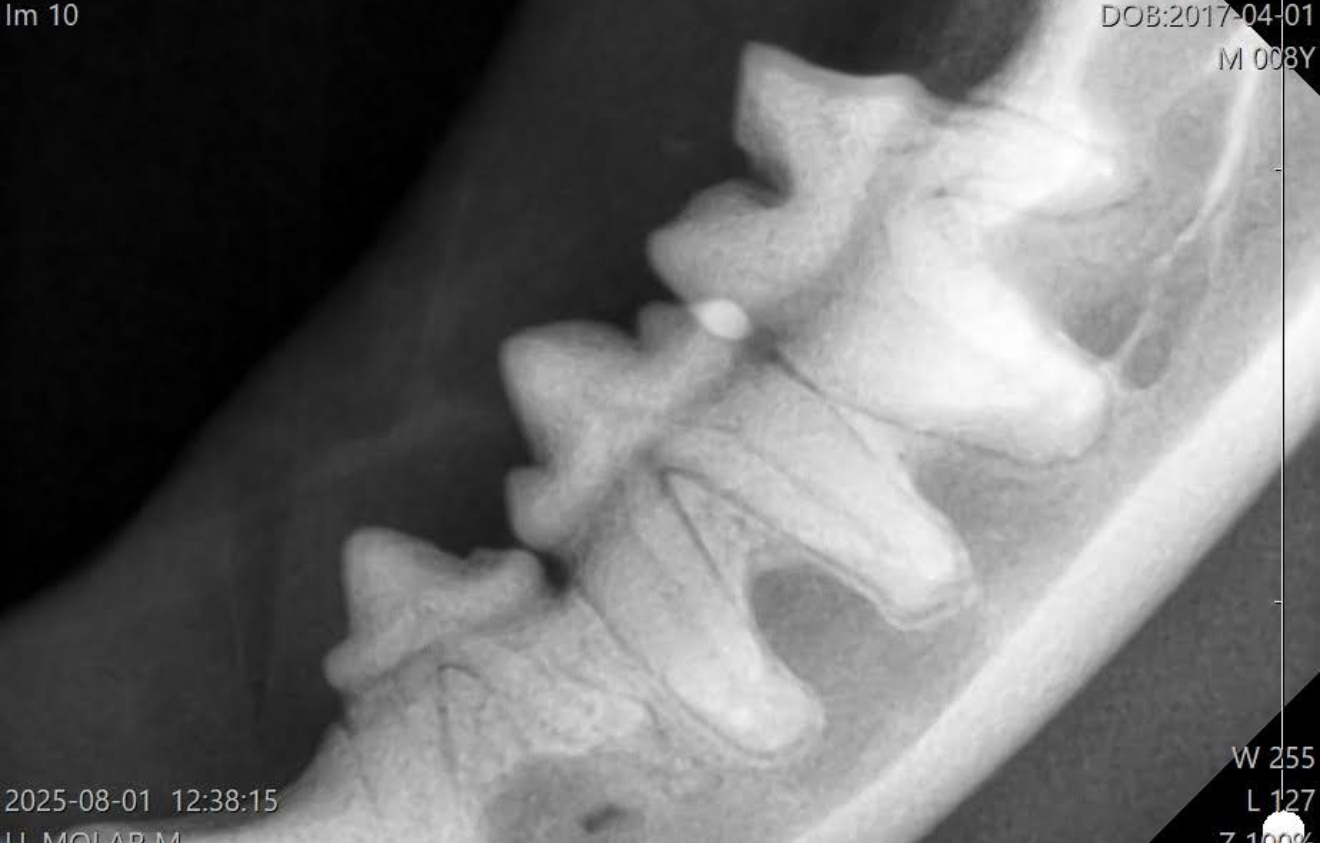

コレは吸収病巣で、骨と歯が同化してきていて

歯周炎も無いし、抜歯も不要な状態です。

歯科レントゲン無しで、抜歯をしようとしたとしても、出来ない状態なので、歯科レントゲン無ければ、抜こうとすると途中で折れるはずです。